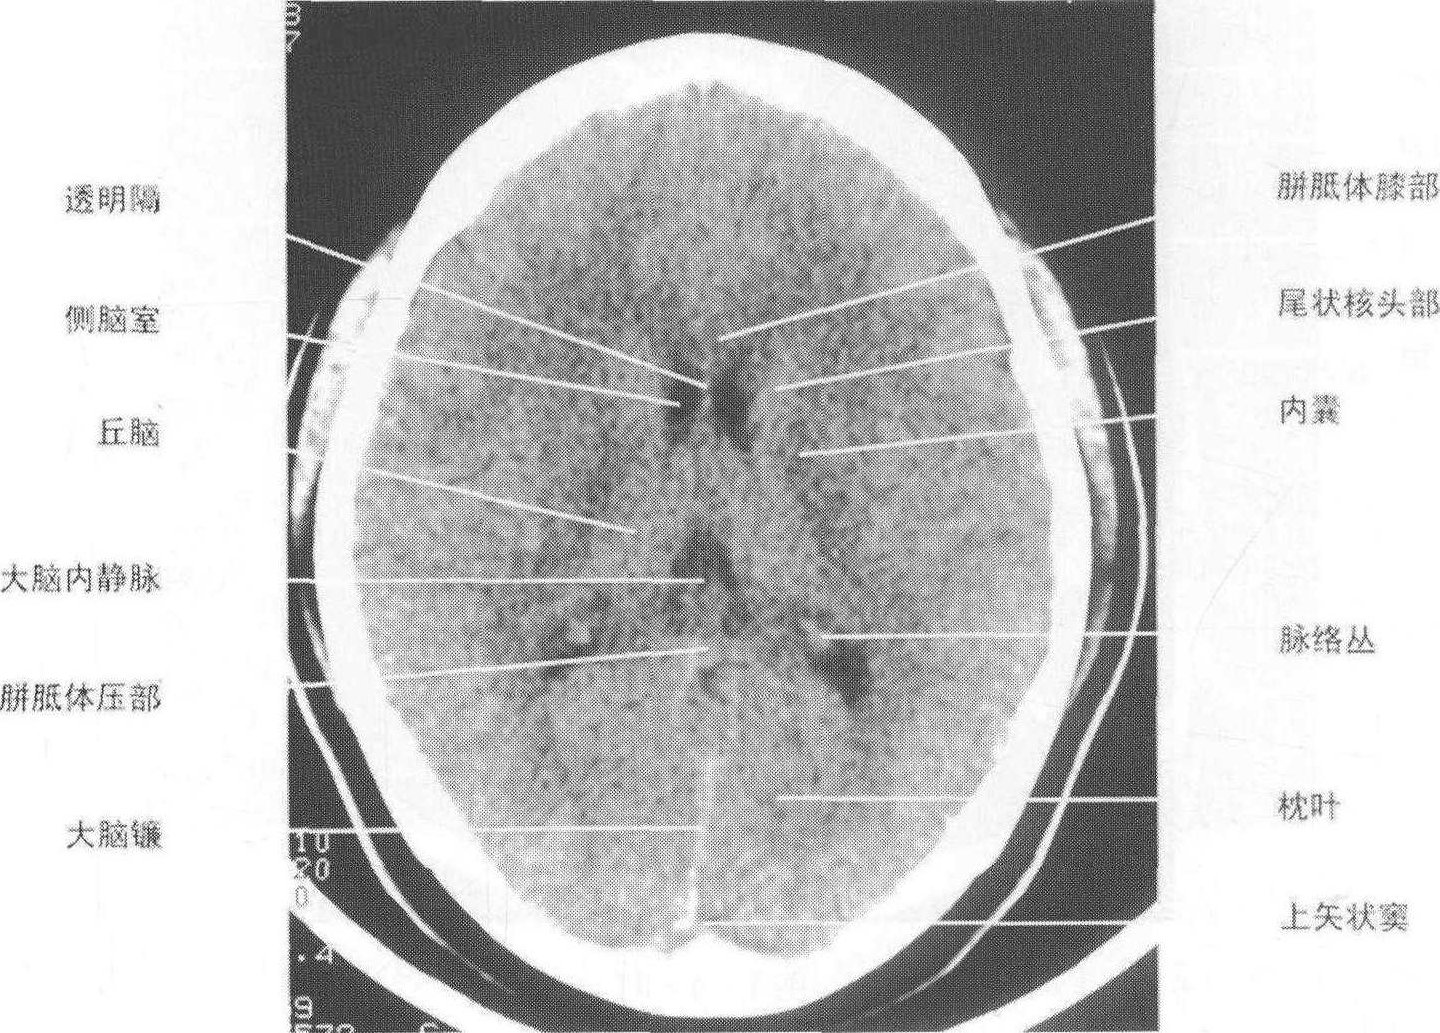

颅脑正常影像学表现(上)

颅脑正常影像学表现(下)